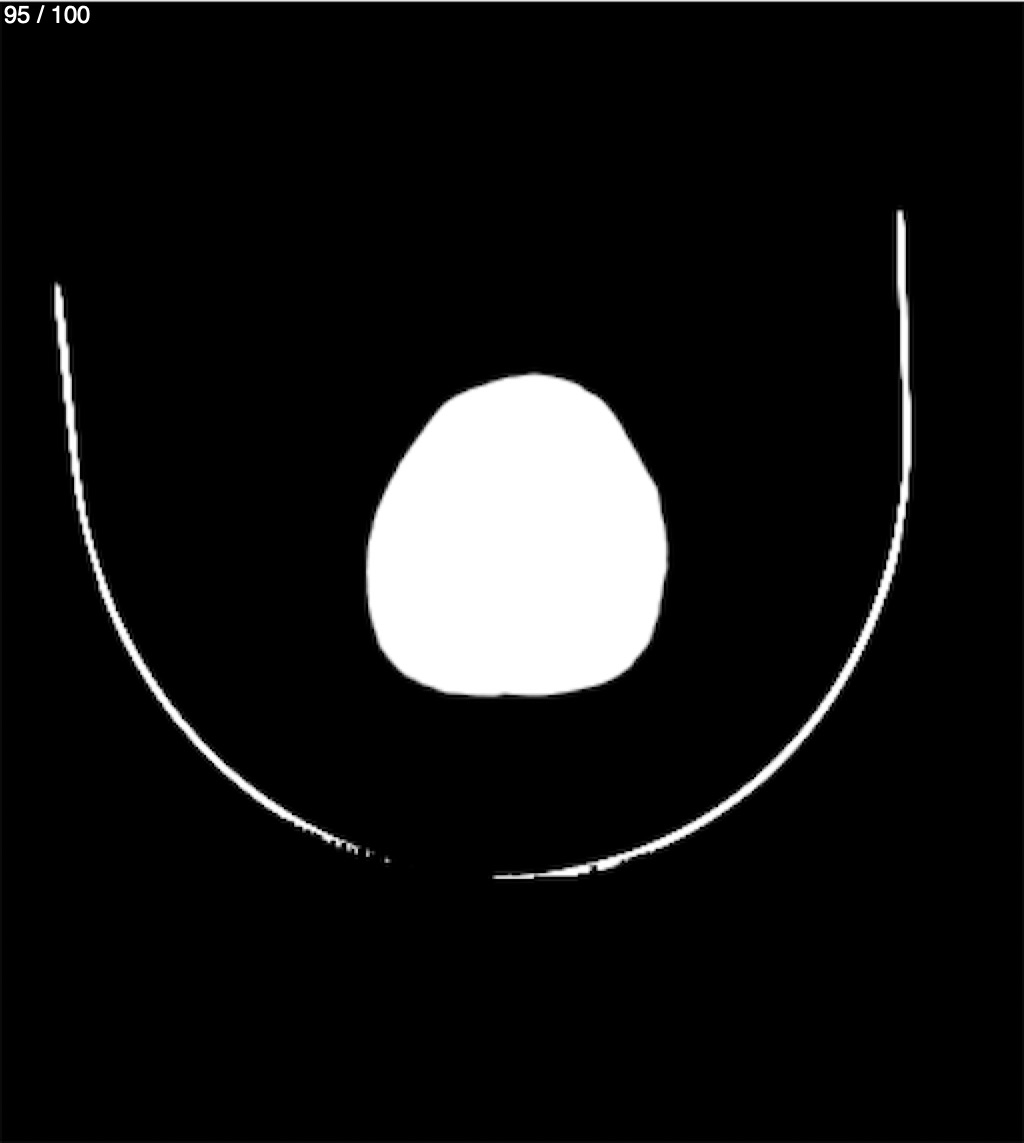

Catarino Perez Escobar 85A - T.C Craneo